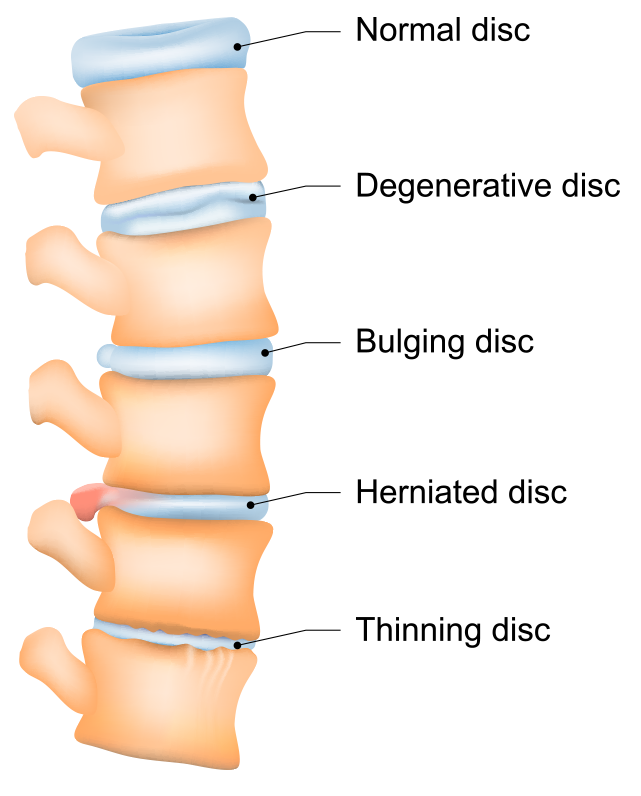

What are the different types of disc problems? | QI Spine

What is the difference between a bulging disc and a herniated disc?